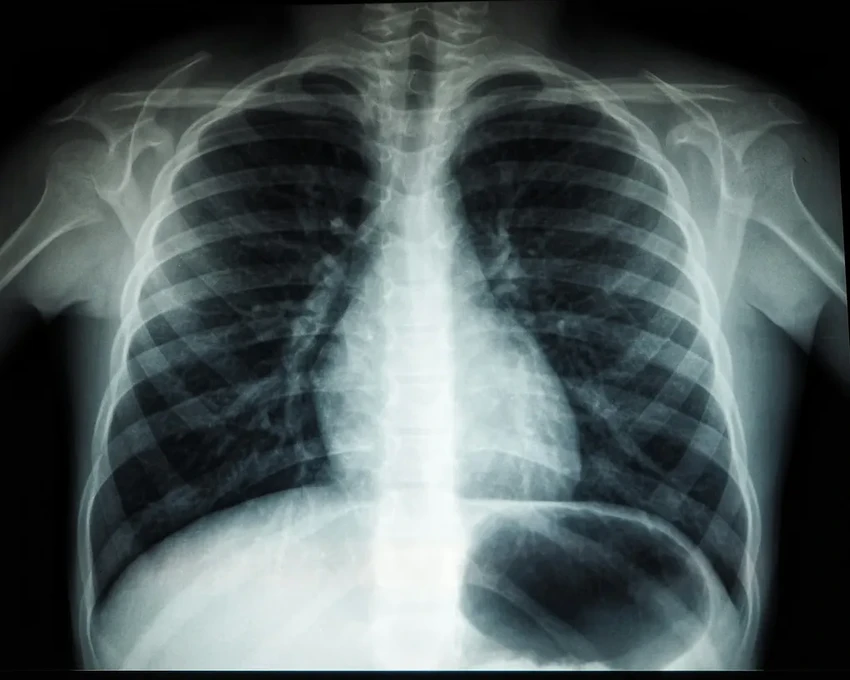

Давайте сравним масштаб бедствия. Грибки убивают людей в шесть раз чаще, чем малярия, и почти в три раза чаще, чем туберкулез. Более того, исследователи предполагают, что в 2019 году из 1,2 миллионов смертей, официально приписанных туберкулезу, около 340 тысяч на самом деле могли быть вызваны сопутствующими грибковыми заболеваниями. Главные убийцы в этом мире — грибки рода Aspergillus (fumigatus и flavus), вызывающие тяжелые легочные инфекции.